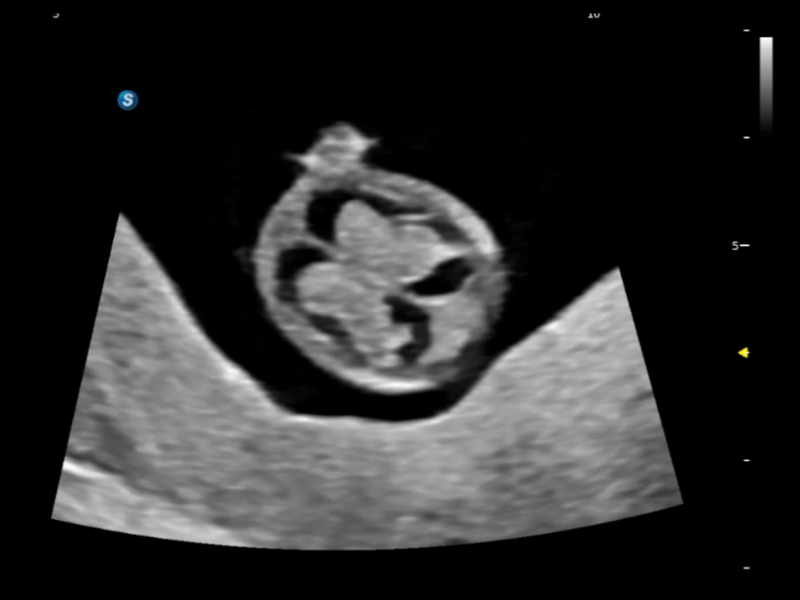

S-Fetus 5.0

S-Fetus (A4C)